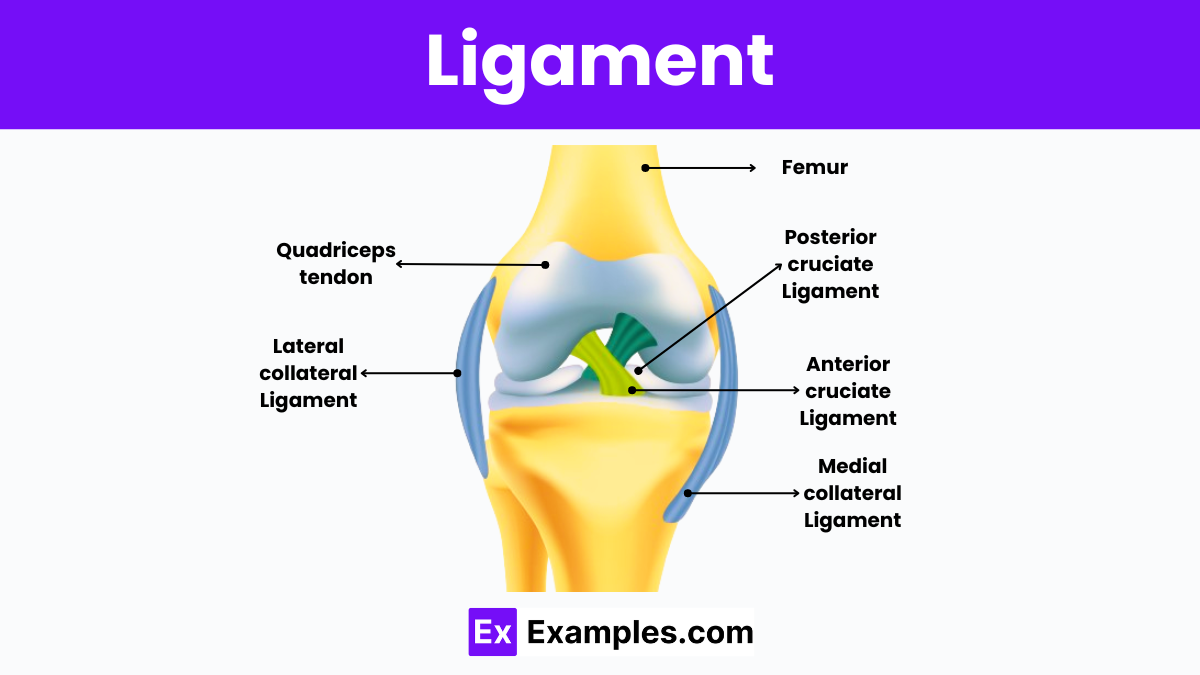

- Lec 3 - Ligaments Diagram | Quizlet

- Ligaments Diagram | Quizlet

- Diagram Of Ligaments | Quizlet